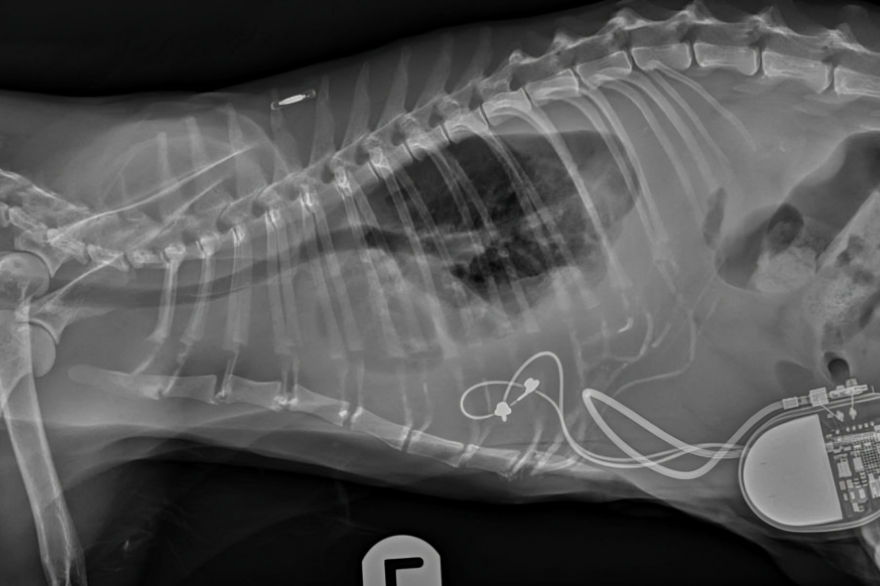

Un estudio reciente demostró que la implantación de un marcapasos epicárdico en felinos se asocia con una baja tasa de complicaciones y una mejor calidad de vida de los gatos que padecen enfermedades cardíacas graves.

Un nuevo estudio dirigido por el Royal Veterinary College (RVC) ha demostrado que la implantación de marcapasos epicárdicos (EP) mejora la calidad de vida de los gatos que padecen enfermedades cardíacas graves.

El uso de la implantación de EP para facilitar la estimulación cardíaca artificial (ACP) resolvió eficazmente los síntomas, incluida la frecuencia cardíaca anormalmente lenta (bradiarritmia) en los gatos.

Si bien este tipo de cirugía generalmente se ha reservado para gatos que presentan síntomas como pérdida de conciencia (síncope), letargo o congestión cardíaca, el estudio ahora confirma que el marcapasos epicárdico es una oportunidad quirúrgica beneficiosa, lo que resulta en una vida más larga y mejor para estos gatos.

El equipo de investigación, dirigido por el Dr. Matteo Rossanese, profesor titular de cirugía de tejidos blandos en animales pequeños y codirector de cirugía de tejidos blandos en el RVC, examinó las complicaciones y los resultados en gatos después de la implantación mediante la revisión de los registros médicos de 39 gatos de cuatro hospitales veterinarios del Reino Unido.